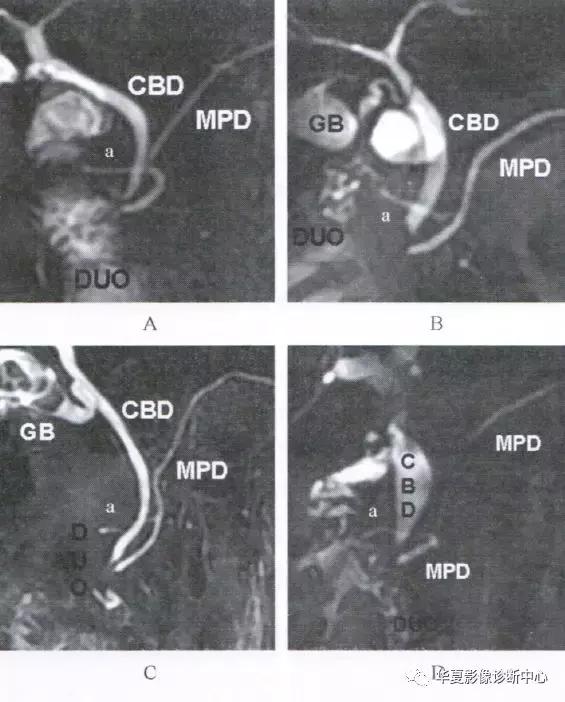

正常主胰管在胰腺内的走行姿态变异较大,在冠状位与斜冠状位MRCP,通常依据主胰管的行程路径分为四型:

1、下降型:最常见,占66%,主胰管自胰尾到胰头缓慢下行;

2、S型:占16%,胰头部主胰管呈S形弯曲;

3、垂直型:占10%,胰头部主胰管下行近乎垂直,平行胆总管;

4、环形:占8%,胰头部主胰管弯曲呈环状。

A:下降型主胰管;B:S型主胰管;C:垂直型主胰管;D:环形主胰管